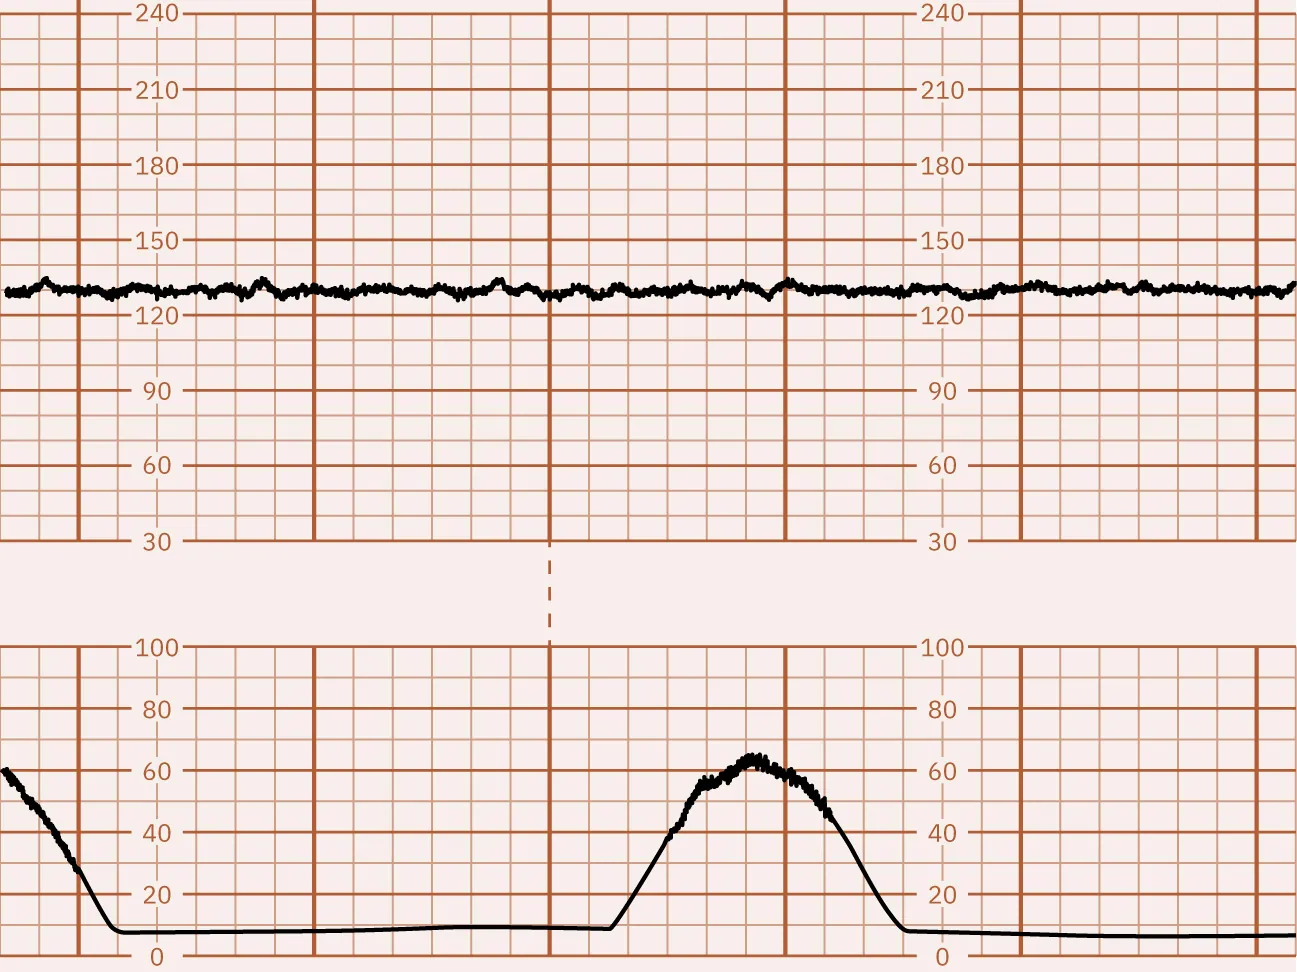

Isolated, sporadic decelerations of at least 15 bpm from the FHR baseline that last 2 to 10 minutes from onset to return to baseline are called prolonged decelerations. The causes of prolonged decelerations are uterine hyperactivity, cord compression, hypotension, placental abruption, seizure, or impending birth. These decelerations are concerning due to the risk for fetal hypoxia. The extent of hypoxia relates to the depth and duration of the deceleration; the deeper and longer the deceleration, the greater the risk of fetal hypoxia. After the prolonged deceleration returns to baseline, the FHR tracing may show decreased variability and tachycardia. These are signs of a significant hypoxic event. Figure 16.14 shows a monitor tracing with an example of a prolonged deceleration.

Fetal heart rate reading indicating prolonged decelerations.

Figure 16.14 Prolonged FHR deceleration This monitor tracing shows tachysystole that leads to a prolonged deceleration. (attribution: Copyright Rice University, OpenStax, under CC BY 4.0 license)